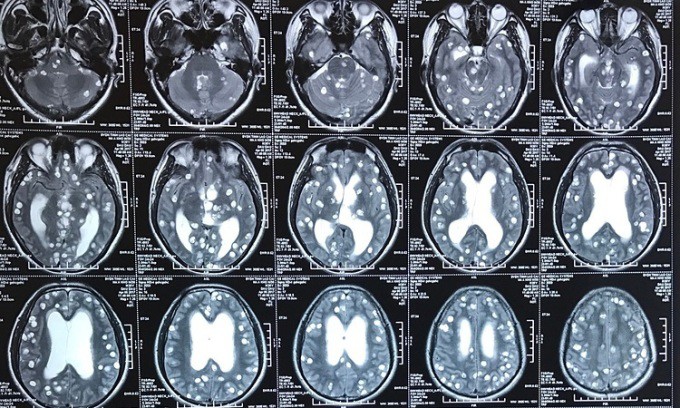

Hình ảnh phim chụp các nang sán ngấm thuốc cản quang chuyển trắng của một bệnh nhân. Ảnh: Bệnh viện cung cấp

Như người đàn ông 62 tuổi ở Bắc Giang, từ năm 2018 xuất hiện nhiều cơn đau đầu dữ dội, chụp cộng hưởng từ chẩn đoán u não. Gần đây, bệnh nhân đau đầu kèm co giật, động kinh, chụp X-quang phát hiện nhiều đốm trắng trên phần mềm cánh tay, làm tổ trên não gây ra những cơn động kinh, rối loạn tâm thần. Bác sĩ phẫu thuật phát hiện khối u là những ổ sán lợn.

Sán não (còn gọi u não do ấu trùng sán dây) là bệnh lý thuộc nhóm nhiễm trùng hệ thần kinh trung ương, gây suy giảm trí nhớ, đau đầu, mờ mắt. Người bệnh sốt cao, đau đầu, nôn do tăng áp lực nội sọ, có thể dẫn đến co giật, liệt mặt ngoại biên (liệt thần kinh số VII, liệt nửa người), tử vong nếu không được chẩn đoán và điều trị kịp thời.